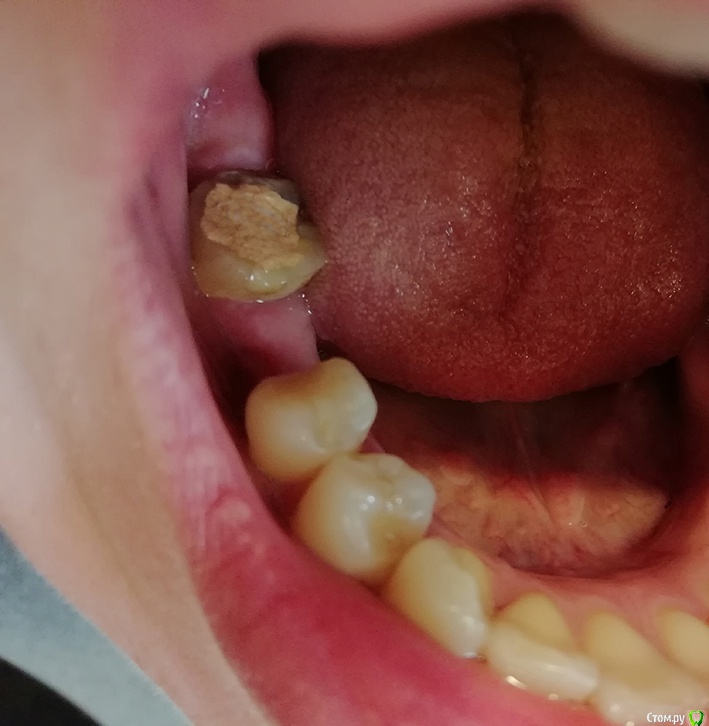

nataganka Опубликовано 20 февраля, 2019 Автор Поделиться Опубликовано 20 февраля, 2019 Дорогие врачи, можно попросить Вас, пожалуйста, структурированно ответить мне. А то я запуталась) сейчас сформулирую еще раз по номерам и фото/снимок прицеплю в это сообщение. Имплантацию 46 сейчас не рассматриваю совсем, понимаю что это лучше, но в ближайшие 5, а то и 10 лет - никак. 45 зуб депульпироваться не будет. Коронки цирконий. Аллергия на всю металлическую бижутерию, опухание, покраснение, в анамнезе присутствует пищевой отек Квинке. С золотыми украшениями дружу. Серебро не носила. 1. Что предпочтительней и долговечней, не рассматривая имплантацию, ставить мост 47-46-45 или предпочтительней вообще оставить все как есть (отсутствие 46), закрыв коронкой только 47? Зуб антагонист 16 опускается. 36 зуб немного скалывается, все это время большая часть нагрузки на него. По этому предполагаю закрыть отсутствие 46 мостом предпочтительней?2. Если лучше мост, то по вкладкам - в 47, требуется все-таки или нет? Просто пломбу? Или стекловолоконный штифт? Металл не рассматриваю. Цирконий сказали чревато трещиной корня? Если вкладка требуется, то где в Москве поставить вкладку из золота?3. Если мост не предпочтителен совсем, то что надежнее восстановить 47 коронкой со вкладкой или пломбой с керамической реставрацией?4. Стоит ли сразу заняться 36 зубом, поставить коронку? И нужна ли туда вкладка? По вкладке вопрос у меня аналогичен 47 зубу. Сейчас на 36 есть небольшие сколы, а также забивается пища между 36 и 37.5. Нужно ли удалять 48 ретинированный зуб перед протезированием? Если острой необходимости нет, я бы предпочла не удалять. За все время жизни он не беспокоил меня ни разу. Если есть необходимость, то удалю, но буду благодарна за контакты хирурга, который сделает это наименее травматичным способом.6. Есть ли по снимку кариес на контактной поверхности 24 зуба со стороны 23 зуба? Или там отложения камня, чистку делаю раз в год. Стоматологи при чистке сомневаются, камень или кариес, на снимок ни разу не посылали. Зуб не болит. Ортопеда нашла благодаря вашему форуму, могу начинать лечение, спасибо, но данные вопросы выше таки у меня остались. А связи с ортопедом кроме телефонного звонка нет, а он очень часто занят, не может ответить, перезванивает. Опять таки письменно проще сформулировать все вопросы. Финансово все что выше озвучила вполне для меня приемлимо, т.е. вполне готова сейчас сделать мост из циркония 47-46-45, коронку из циркония на 36, вкладки (если требуются?) и удалить 48. Ссылка на комментарий